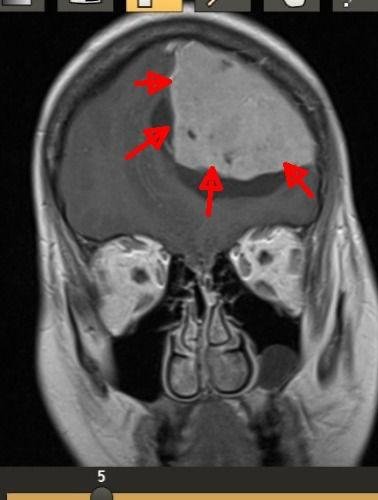

وتفصيلاً؛ بعد إجراء الفحص بالرنين المغناطيسي على الرأس تبيّن وجود ورم كبير الحجم في الفص الأيسر من الدماغ، ويضغط بشكلٍ مباشر على مراكز عصبية وحيوية ومن بينها مراكز النطق، ليقرر الفريق الجراحي بقيادة رئيس جراحة المخ والأعصاب د. عصام شبشوب إجراء عملية بالغة الدقة استغرقت حوالي 4 ساعات، تم خلالها الاستئصال الكلي للورم مع الحفاظ على سلامة الوظائف العصبية للمراكز الدماغية الحساسة المتاخمة للورم مثل مراكز التحكم في النطق والحركة؛ وذلك عبر استخدام تقنيات جراحية دقيقة وأجهزة متطورة مثل جهاز تفتيت وشفط الأورام بالموجات فوق الصوتية، وتمت إفاقة المريضة من التخدير مباشرة بعد العملية وهي لا تزال في غرفة العمليات، وكانت متجاوبة وبدون وجود أي مضاعفات وهي الان في صحة جيدة وتحسن مستمر -ولله الحمد-.